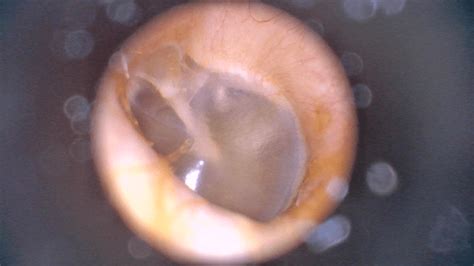

The tympanic membrane, also known as the eardrum, plays a crucial role in our auditory system. It is a thin, semi-transparent membrane that separates the external ear canal from the middle ear. In certain conditions, the tympanic membrane can become bulging, which can cause discomfort, hearing loss, and other complications. A bulging tympanic membrane is characterized by an outward protrusion of the membrane, often accompanied by redness, swelling, and fluid accumulation in the middle ear.

The symptoms of a bulging tympanic membrane can vary depending on the underlying cause and severity of the condition. Common symptoms include ear pain, hearing loss, and discharge from the ear. In some cases, a bulging tympanic membrane can also cause vertigo, tinnitus, and a feeling of fullness in the ear. To diagnose a bulging tympanic membrane, a healthcare professional will typically perform a physical examination of the ear, using an otoscope to visualize the tympanic membrane.